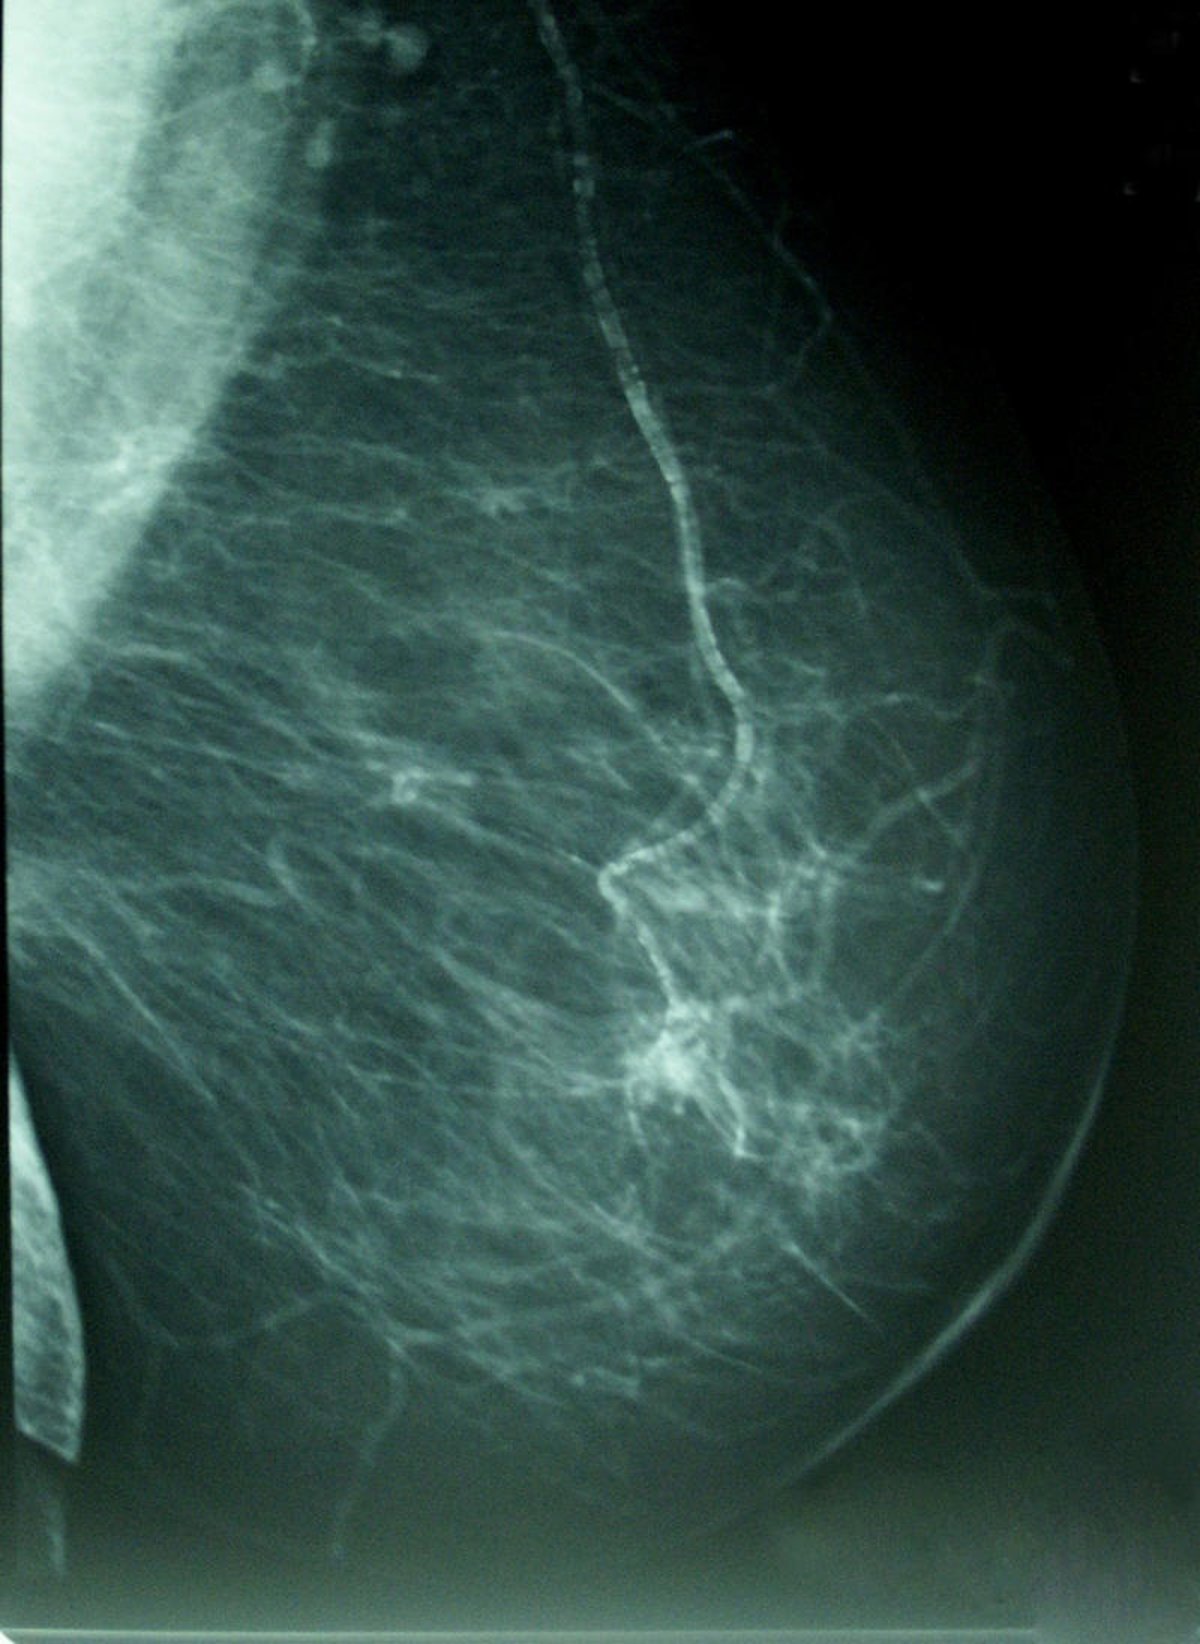

Cáncer De Mama, Densidad Mamográfica

Cada año se detectan en España unos 18.000 nuevos casos de cáncer de mama pero, gracias a los programas de cribado que hay implantados en las comunidades autónomas, la mayoría de pacientes son diagnosticadas precozmente con tumores de menos de 2 centímetros.

Pero, más allá de la importancia de las campañas de 'screening', este oncólogo anima a las mujeres a "mentalizarse" de que "si se notan algún nódulo en la mama que no hubieran percibido previamente y que no disminuya con el paso de los días, deben consultar para que se inicie un estudio adecuado".